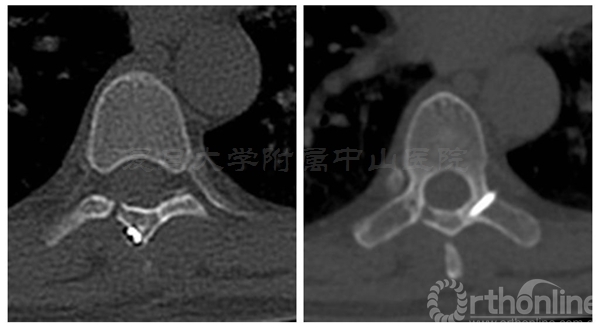

术后三个月患者腰背痛完全缓解,肌力已恢复至5级,下肢麻木感消失。CT显示:椎板截骨面已骨性愈合,无移位,椎管容积与术前无明显差异

术后半年CT显示两侧椎板截骨面均已骨性愈合,椎管体积无减少。MRI显示椎管内脊膜瘤无复发